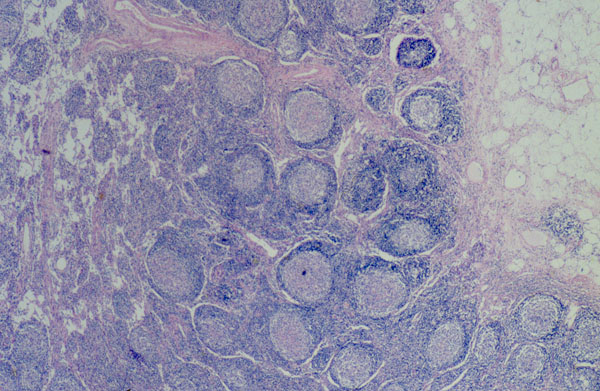

Микропрепараты: Лимфогранулематоз и Нодулярный Склероз

Раздел: Секреты мастерства